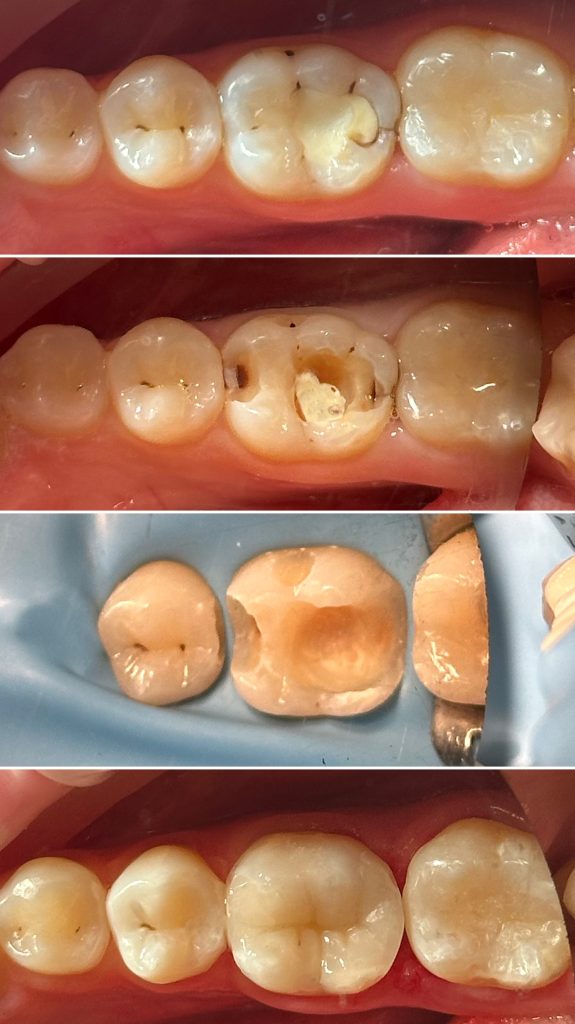

• Диагностика и лечение кариеса и его осложнений (пульпиты, периодонтиты)

• Художественная реставрация фронтального и бокового участка зубов

2022 год – «Прямая реставрация.Боковой сегмент.» Игорь Гудыма